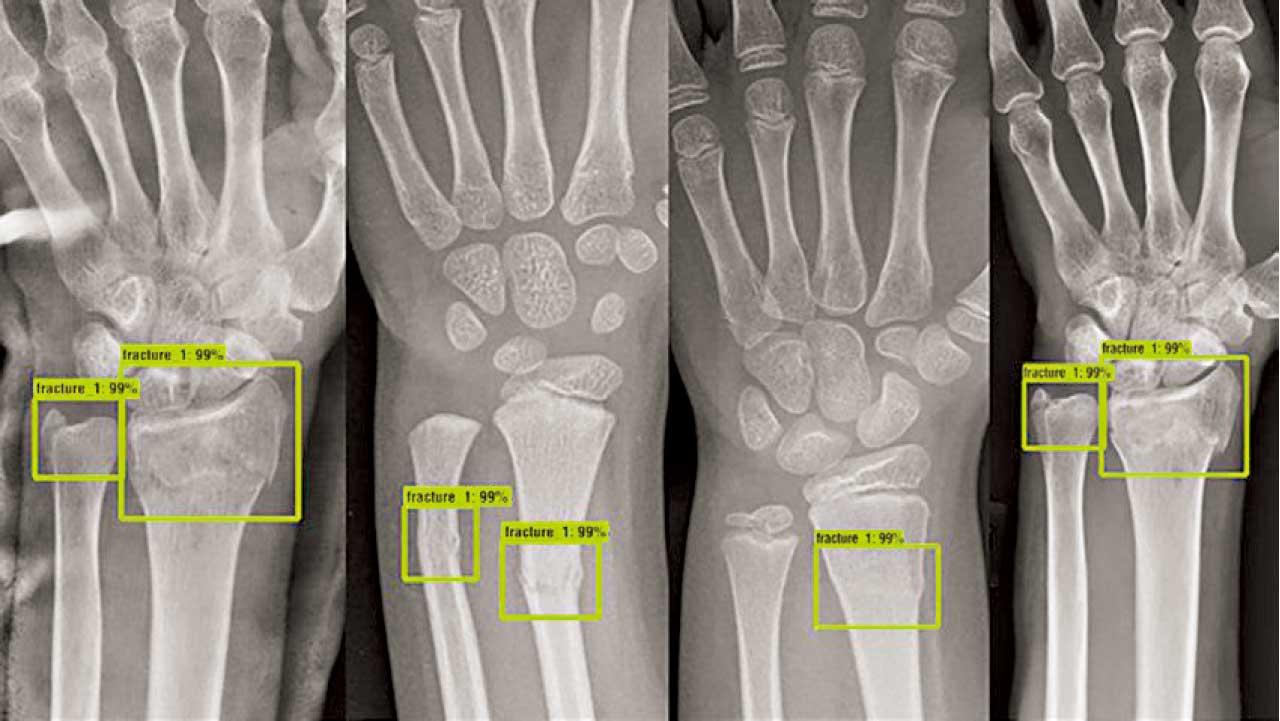

生物資訊學在診斷方面發揮舉足輕重的作用。本港有人工智能初創公司正與醫管局合作,利用先進的機器學習演算法,分析X光和MRI等醫學影像數據,能準確檢測肺炎和骨折等疾病。這些人工智能工具可協助放射科醫生作更快、更精確的診斷。